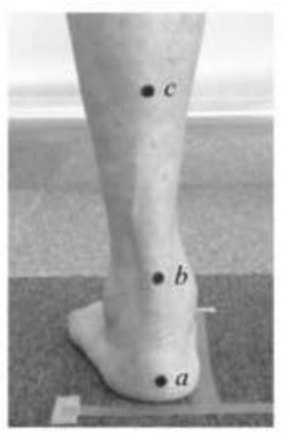

2. 腳跟與小腿相對位置(LHA): 依下圖中的cb連線與ab連線之交叉角度表示

3. 腳跟與接觸地面相對位置(HA) :依下圖中的ab連線與地面水平線之交叉角度表示